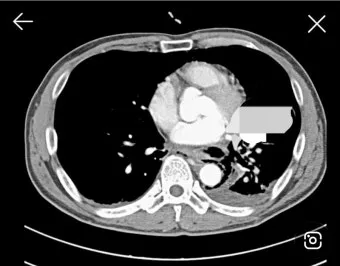

3단계, 흉부 초음파·CT 검사입니다.

특히 초음파는 수십 mL 수준의 적은 양 흉수도 찾아내는 데 도움이 되고, 어디에 얼마나 모여 있는지를 파악해 나중에 흉강천자(물을 뽑는 시술)를 할 위치를 잡는 데 쓰입니다.:contentReference[oaicite:22]{index=22}